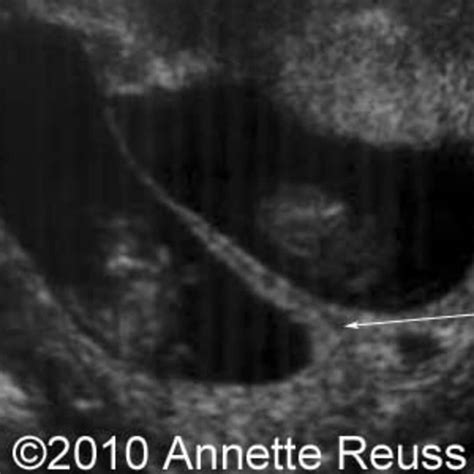

In the realm of medical diagnostics, the Twin Peak Sign is a critical indicator that can significantly aid in the identification of certain conditions. This sign, characterized by its distinctive dual-peak pattern on diagnostic imaging, plays a pivotal role in the early detection and management of various health issues. Understanding the Twin Peak Sign and its implications can enhance diagnostic accuracy and improve patient outcomes.

Understanding the Twin Peak Sign

The Twin Peak Sign is a radiologic finding observed in imaging studies such as X-rays, CT scans, and MRIs. It is named for its characteristic appearance, which features two prominent peaks or elevations. This sign is particularly relevant in the context of musculoskeletal and cardiovascular diagnostics. The Twin Peak Sign can indicate conditions such as fractures, dislocations, and certain types of tumors. Recognizing this sign can help healthcare professionals make more informed decisions about patient care.

Clinical Significance of the Twin Peak Sign

The clinical significance of the Twin Peak Sign lies in its ability to provide early and accurate diagnostic information. For instance, in orthopedic settings, the Twin Peak Sign can be a crucial indicator of fractures, especially in complex or comminuted fractures where the bone fragments are scattered. Early detection of such fractures can lead to timely intervention, reducing the risk of complications and promoting better healing.

In cardiovascular diagnostics, the Twin Peak Sign can be observed in conditions such as aortic dissection, where the aorta's layers separate. This sign can help differentiate between true and false lumens, aiding in the diagnosis and management of this life-threatening condition. The ability to quickly and accurately identify aortic dissection is essential for initiating appropriate treatment and improving patient survival rates.